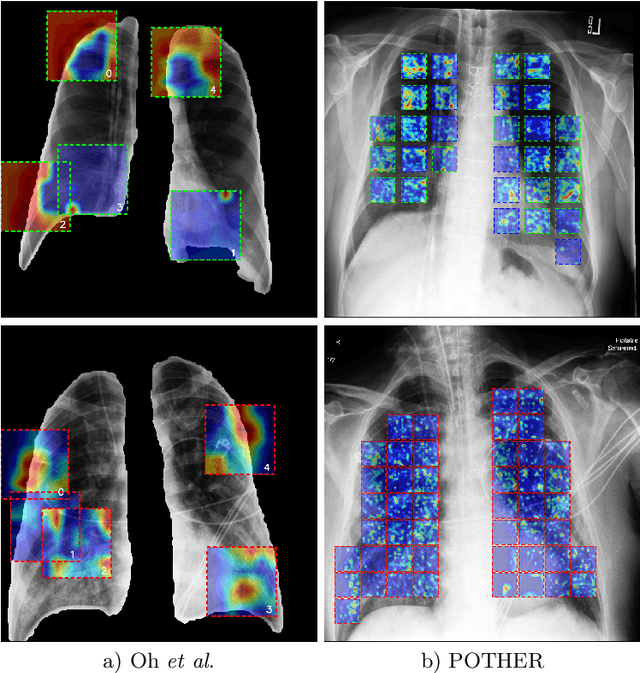

Abstract:A critical step in the fight against COVID-19, which continues to have a catastrophic impact on peoples lives, is the effective screening of patients presented in the clinics with severe COVID-19 symptoms. Chest radiography is one of the promising screening approaches. Many studies reported detecting COVID-19 in chest X-rays accurately using deep learning. A serious limitation of many published approaches is insufficient attention paid to explaining decisions made by deep learning models. Using explainable artificial intelligence methods, we demonstrate that model decisions may rely on confounding factors rather than medical pathology. After an analysis of potential confounding factors found on chest X-ray images, we propose a novel method to minimise their negative impact. We show that our proposed method is more robust than previous attempts to counter confounding factors such as ECG leads in chest X-rays that often influence model classification decisions. In addition to being robust, our method achieves results comparable to the state-of-the-art. The source code and pre-trained weights are publicly available (https://github.com/tomek1911/POTHER).